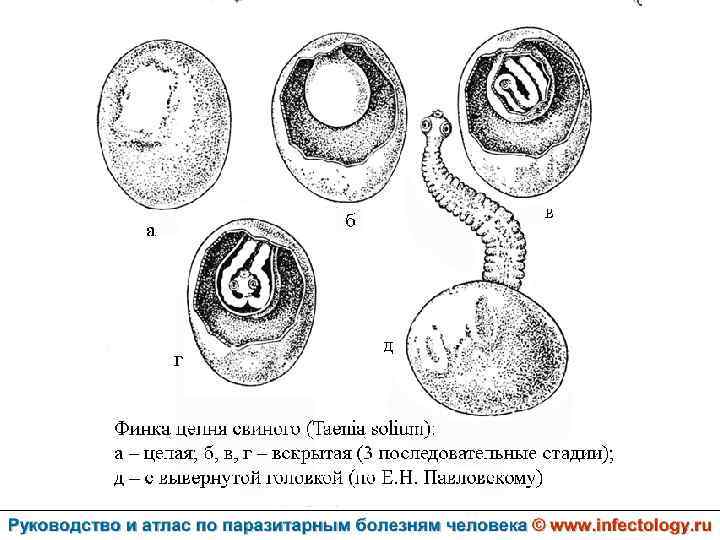

Цистицеркоз (шифр по МКБ 10 - B 69) – биогельминтоз, который вызывается паразитированием в тканях и органах человека и животных личиночной стадии цепня вооруженного – цистицерка (Cysticercus cellulosae) Болезнь проявляется разнообразными симптомами в зависимости от локализации цистицерков.